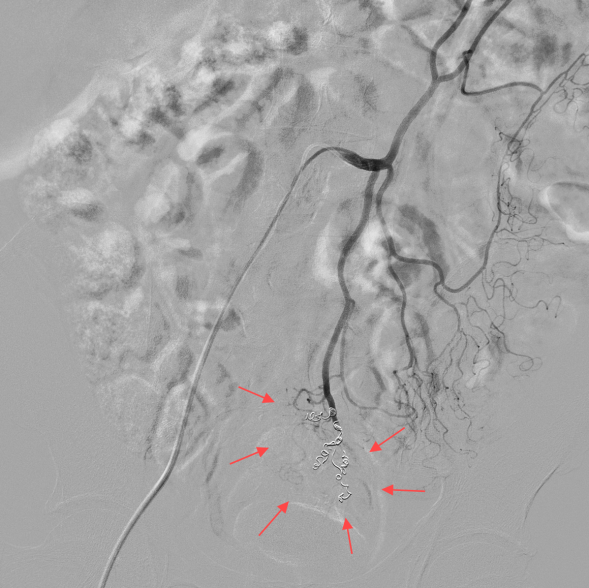

术中肠系膜下动脉造影见直肠上动脉末梢丰富的痔血管显示